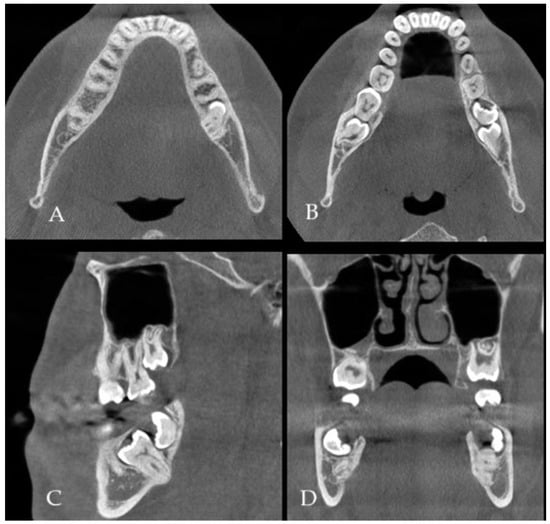

Six months after surgery, the wound still had a small dehiscence (A). No fluid accumulation was seen; however, the patient reported cases of some loose bone secretion. Control panx revealed good bone volume, proper healing in the deeper layers, no formation of granulation tissue, nor any bone inflammation or signs of bone resorption or any radiolucent area in the grafted bone (B). A different comparable case of a 51-year-old male with hypertension and with active inflammation is presented in (C). In the main case (B), the used plating systems were stable without any local bone changes. The used panx is very limited in establishing full bone changes; however, it is suitable enough for early screening purposes for bone changes estimation. In the presented case, without any presence of bone loss, bone resorption, formation of cystic cavities, bone inflammation, or the presence of granulation tissue with partially unhealed or necrotic bone parts and without typical halo marks and radiolucencies, there was no necessity for additional CBCT evaluation (A,B). The patient (B) was asymptomatic, and the wound had been stable for the past six months. The patient finally decided on a revision surgery and wound debridement. Before the surgery, a microscopic specimen evaluation from the wound revealed colonization of part of the bone with Klebsiella pneumoniae and Staphylococcus aureus (D). Intraoral Biseptol (2 × 980 mg per day, sulfamethoxazole with trimethoprim, Adamed Pharma S.A., Czosnów, Poland) was used for 10 days, followed by local antiseptic agents three times per day, 0.1% CHX solution (gluconate chlorhexidine, Eludril, Pierre-Fabre Oral Care, Paris, France), and 3% H202 (hydrogen peroxide, Farmina, Kraków, Poland) as preparation for revision surgery. The lack of any worrisome radiological signs in a typical panx is a very good finding, especially the appearance of bone healing was very good without any worrisome factors, bone loss, and lack of its remodeling, suggesting an uneventful bone grafting procedure. In a six-month time frame, a very good remodeling process was established regardless of the constant presence of a dehiscence and unhealing wound in the oral cavity. This case presents how an oral wound (A) does not correlate entirely with any radiological changes in a six-month time frame (B). Furthermore, any small local soft and bone tissue problems do not seem to correlate with other changes, which seems to correspond to the fact that just major and more advanced bone inflammation (red arrow, comparable case—(C)), necrosis or local loss of healing, scattered radiolucencies (blue arrow) with bone loss are visible in the radiological evaluation, especially when a bigger scope of bone is changed and inflamed (yellow arrow), as presented in the comparable case (C). The loss of proper bone structure in the early six months of panx visualization is a very troublesome factor, which requires both improved diagnostics with CBCT and revision surgery with microscopic and histopathologic specimen evaluation. When a purulent or granulation fistula is present, serious bone inflammation with loss of bone volume is mostly present. Regardless of the type of panx used and CBCT, without any progression of worrisome symptoms, a typical screening with a panx radiograph is sufficient. Both presented cases required vision surgery with microbiological and histopathological wound evaluation. Patient (B) was scheduled for a revision surgery that consisted of wound debridement, curettage, and ostectomy until the levels of healed and bleeding bone were noted. Some samples were taken for both microbiological and histopathological evaluation. When wound healing is not sufficient in each case, both improved radiology with CBCT or histopathology should be taken to fully evaluate the scope of the problem in the wound, to evaluate whether it is related to the surgical procedure, bone inflammation, microbiological contamination, or if there is the necessity for a wound debridement or bone removal.